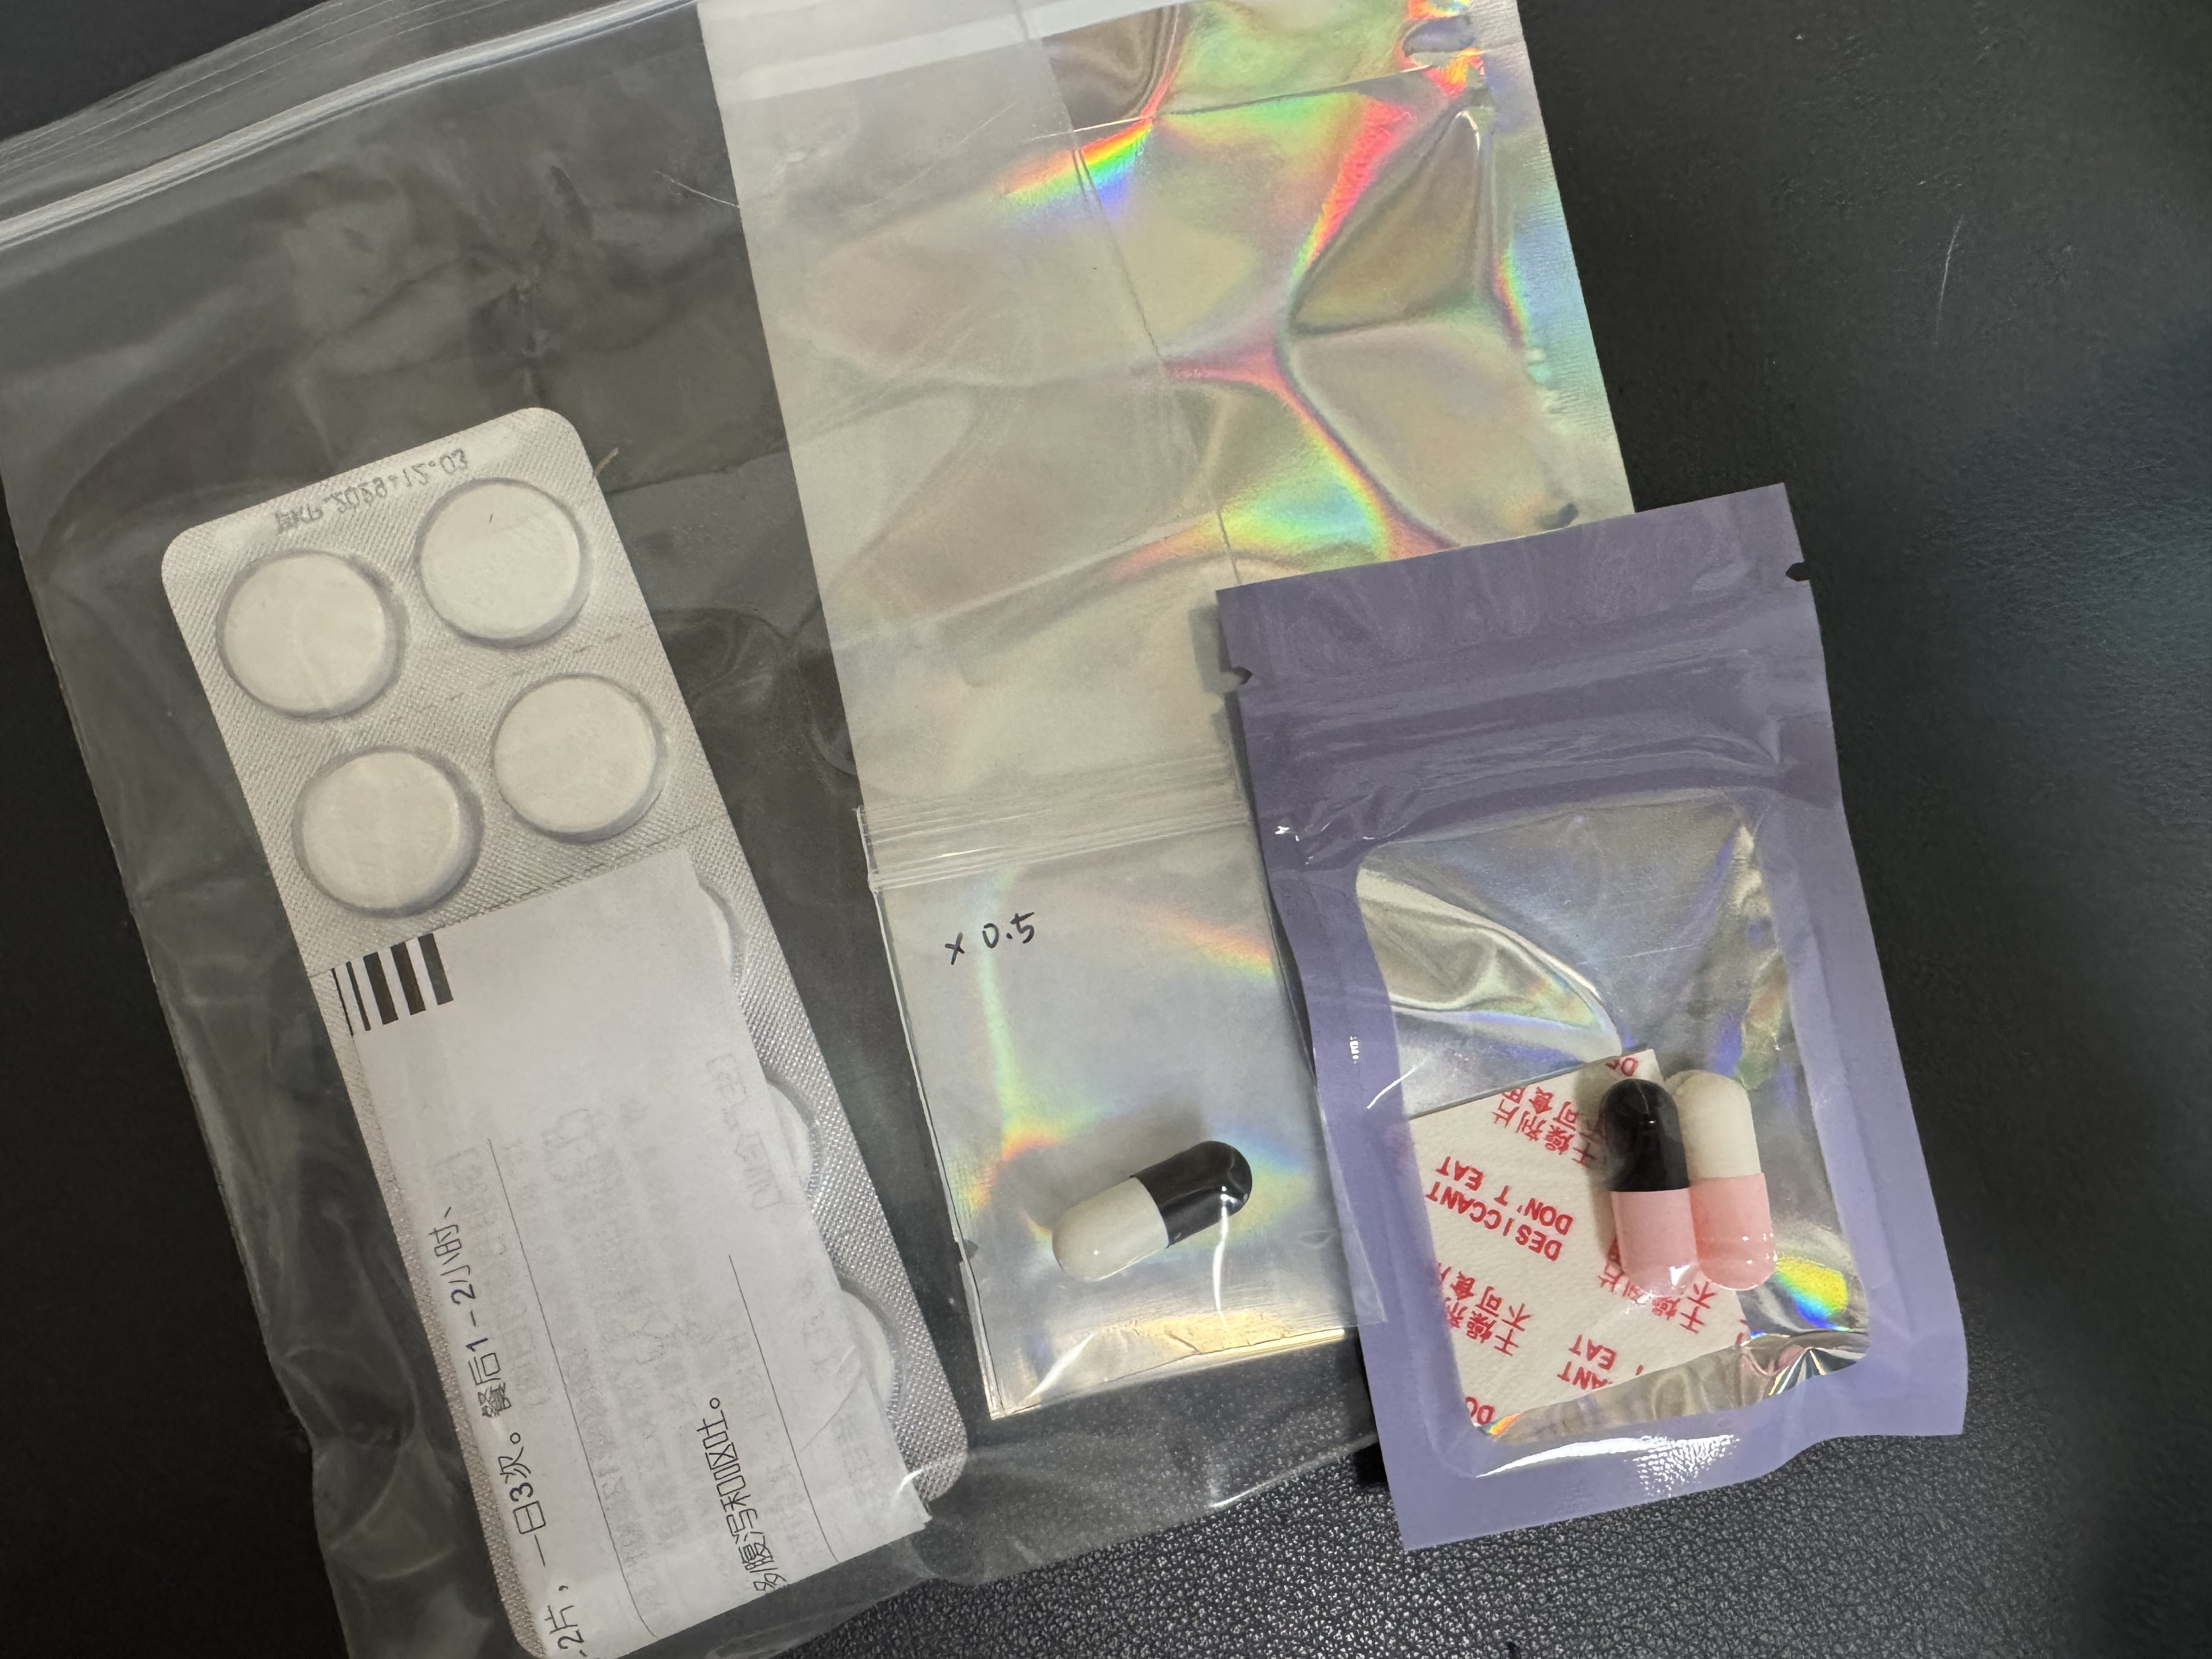

对于药物过量引起的中枢神经系统副作用,有一些不常见或常见的药物来控制症状。

评论区欢迎补充 https://t.co/7S4tGVDEM5